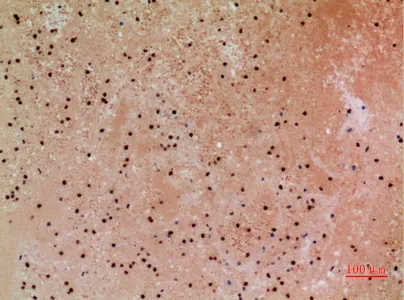

FOXP1 Rabbit Polyclonal Antibody

Cat: APRab11113

Size1:50μl Price1:$118

Size2:100μl Price2:$220

Size3:500μl Price3:$980